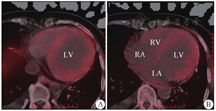

LV:左心室;LA:左心房;RV:右心室;RA:右心房;A、B:心肌弥漫性摄取炎症显像剂